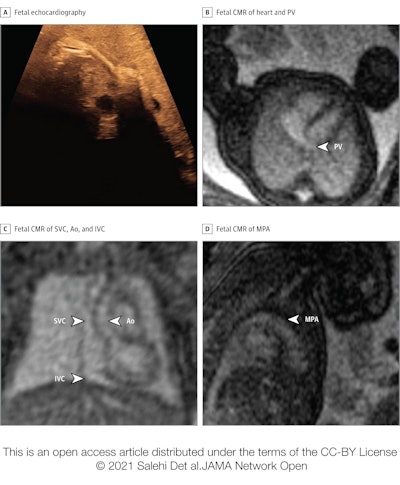

Congenital heart defects are typically identified in utero by echocardiography, but sometimes that modality proves inconclusive due to inadequate acoustic windows. In recent years researchers have developed an MR-compatible Doppler ultrasound device that allows for the acquisition of high-resolution fetal cardiovascular MR (CMR) images without postprocessing.

Salehi and colleagues sought to investigate the efficacy of fetal CMR after inconclusive echocardiography, as well as whether its use resulted in any patient management or parental counseling changes. The team conducted a study of 31 fetuses referred for cardiovascular MRI at Skåne University Hospital in Lund between January 2017 and June 2020; fetuses had a median gestational age of 36 weeks.